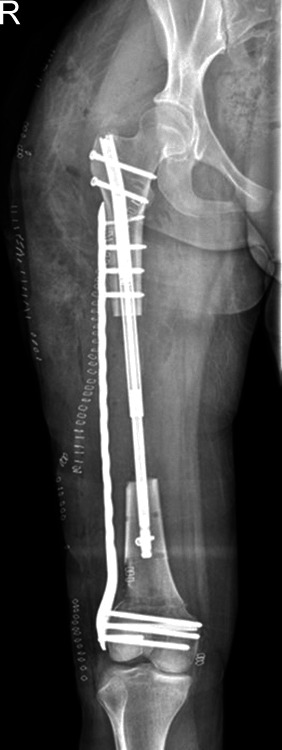

Aim: The treatment of massive diaphyseal tibial bone defects remains challenging with poor results seen from treatment modalities other than bone transport (BT). Current methods of BT require lengthy periods in a circular external fixator. Despite recent modifications in BT techniques via circular external fixator such as multifocal transport and immediate intramedullary nailing after docking, circular external fixation remains poorly tolerated with a high complication profile. Newer technologies such as magnetic lengthening nails have shown promise to provide alternatives to BT without resorting to long-term circular external fixation. Plate-assisted bone segment transport (PABST) has demonstrated success as an all-internal BT technique. Prior case reports have shown a modest ability to treat massive defects with varying success.

Technique: A novel all-internal cable and pulley augmentation to a PABST technique for a massive (185 mm) tibial defect was utilised during a retrograde transport. The authors describe a patient scenario in which this augment allowed continued transport that could not be treated with an additional Precice nail recharge.

Conclusion: Augmentation of PABST with a cable and pulley construct can successfully treat massive diaphyseal defects.

Clinical significance: This cable and pulley modification to PABST allows for the treatment of massive tibial defects without the need for magnetic lengthening nail exchange or conversion to external fixation.